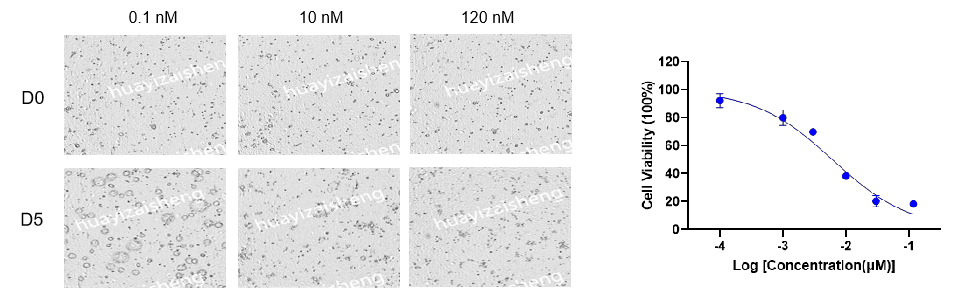

单药药效评价